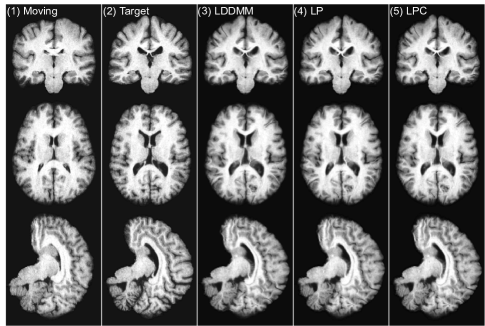

In this experiment, we use a sliding window stride of 14 for both the prediction network and the correction network during evaluation. We mainly compare the following three LDDMM-based -methods: (i) the numerical LDDMM optimization approach (LO) as implemented in PyCA, which acts as an upper bound on the performance of our prediction methods; and two flavors of Quicksilver: (ii) only the prediction network (LP) and (iii) the prediction+correction network (LPC). Example registration cases are shown in Fig. 9.

LO is the algorithm that our predictive registration approaches (LP and LPC) are based on. Hence, LP and LPC are not expected to show improved performance with respect to LO. However, similar performance for LP and LPC would indicate high quality predictions. Indeed, Table 3 shows that our prediction+correction approach (LPC) performs similar (with respect to the other registration methods) to LO. A slight performance drop with respect to LO can be observed for LPC and a slightly bigger performance drop for LP, which only uses the prediction model, but no correction model.

To assess statistical equivalence of the top performing registration algorithms we performed paired two one-sided tests (paired TOST) [71] with a relative threshold difference of 2%. In other words, our null-hypothesis is that methods show a relative difference of larger than 2%. Rejection of this null-hypothesis at a significance level of α=0.05/204𝛼0.05204\alpha=0.05/204 then indicates evidence for statistical equivalence. Table 4 shows the paired TOST results. For a relative threshold difference of 2% LPC can be considered statistically equivalent to LO for all four datasets and to many of the other top methods (e.g., LPC vs. SyN on MGH10 and IBSR18).

Overall, these statistical tests confirm that our prediction models, in particular LPC, are highly competitive registration algorithms. Computational cost, however, is very small. This is discussed in detail in Sec. 3.4.

3.2.3 Choosing the correct “correction step”

As shown in Sec. 3.2.2, LPP, LPC2 and LPC3 all result in label overlapping scores which are similar to the label overlapping scores obtained via LPC. This raises the question which method should be preferred for the correction step. Note that among these methods, only LPC is specifically trained to match the LDDMM optimization results and in particular to predict corrections to the initial momentum obtained by the prediction model (LP) in the tangent space of the moving image. In contrast, LPP, LPC2 and LPC3 lack this theoretical motivation. Hence, it is unclear for these methods what the overall optimization goal is. To show what this means in practice, we computed the determinant of the Jacobian of the deformation maps (Φ1superscriptΦ1\Phi^{-1}) for all voxels for all four registration cases of [33] inside the brain mask and calculated the histogram of the computed values. Our goal is to check the similarity (in distribution) between deformations generated by the prediction models (LP, LPC, LPP, LPC2, LPC3) in comparison to the results obtained via numerical LDDMM optimization (LO).